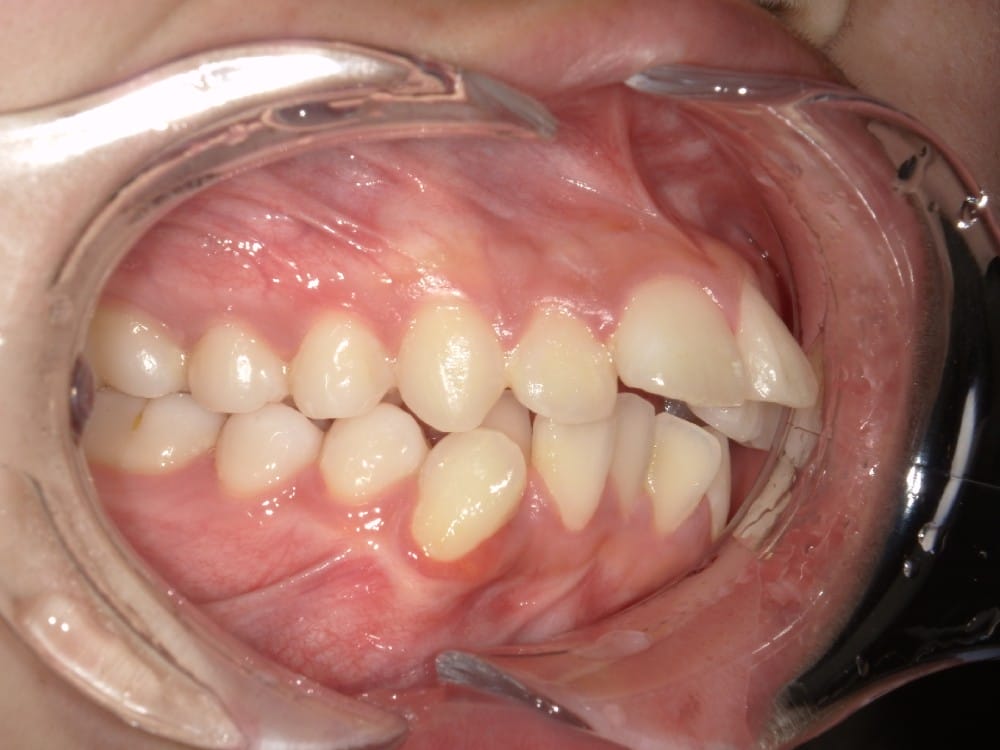

実際の治療前後の写真

before

after

前歯を数ミリ後退させるだけでも、唇の位置は明確に変わります。

横顔ではEラインとの距離が縮まり、「横顔がすっきりした」「口が自然に閉じられるようになった」と感じられる方が多いです。

また、歯の角度を適切にコントロールすることで、歯茎ごと前に出ているように見えていた印象が改善するケースもあります。歯列が原因であれば、外科手術を行わずに目標に近づける可能性が高いのです。